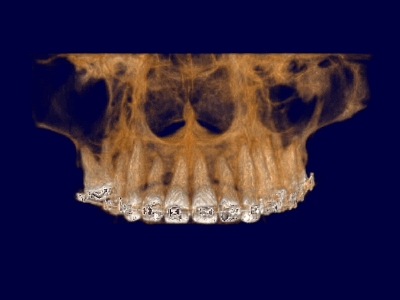

Pro Patient: Our state-of-the-art cone-beam computed tomography (CBCT) technology could selectively image the sinus, oral maxillofacial, para-nasal sinuses, ear & throat regions.

We practice the ALARA principle; (As low as Reasonably Achievable) all scans are restricted to the “Field of View” of your dentist’s prescription. It is taken using (1) pulsed x-ray exposure protocols, (2) real-time-automatic exposure control of the x-ray dose based on the patient’s actual bone density & (3) high resolution digital x-ray image sensors. These factors lead to a significant reduction in x-ray exposure equivalent to only 10% of the x-ray dose of a medical CT-Scan.

Proactive Dental Management thru our 3D Imaging Manipulation Software

With Oral Maxillofacial CT Scans, your dentist enhances his ability to proactively manage your health concern thru accurate diagnosis & better treatment planning. Moreover, the patient benefits from a painless,low radiation dose CT Scan procedure.